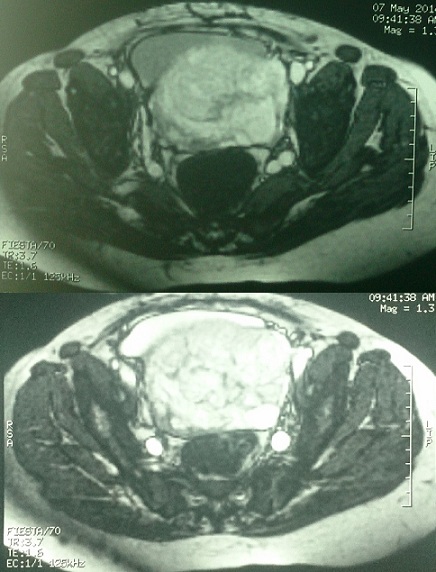

Placenta percreta avec envahissement vésical

Le placenta percreta se définit par une invasion placentaire étendue avec atteinte conjuguée du myomètre et de la séreuse utérine et par un envahissement plus ou moins important des organes pelviens adjacents. Les complications maternelles sont représentées par les risques hémorragiques, de rupture utérine, d'envahissement vésical, de sténose ou fistule urétérale et digestive. Une femme de 32 ans avec comme ATCD quatre grossesses dont 2 accouchements par césarienne a été hospitalisée à 33 SA devant l'apparition de métrorragie minime, une échographie/doppler obstétricale et une IRM avaient montré un placenta recouvrant ayant un aspect perccreta. La patiente a développé par la suite à 5 jours de son admission des métrorragies foudroyantes de grande abondance ayant nécessité son admission d'urgence au bloc opératoire. L'exploration chirurgicale avait identifié un placenta totalement recouvrant antero-postérieur envahissant le segment inférieur et le trigone /rétro trigone vésical, une hystéroraphie a permis l'extraction d'un nouveau-né de sexe féminin, puis réalisation d'une hystérectomie sub-total hautement hémorragique laissant en place un placenta inextirpable hautement adhérant a la face postérieur de la vessie et constatation d'un délabrement vésical important. Après repérage des deux méats urétéraux, intubation et montée de sondes urétérales des deux cotés extériorisée en trans-vésico-pariétal puis fermeture laborieuse sur sonde double courant de la vessie dont la paroi postérieur ne se résumait qu'à une fine paroi muqueuse reposant sur le placenta, la patiente a présenté pendant l'intervention plusieurs épisodes d'hypotension et a été transfusée en per et post opératoire de 8 culots globulaires.